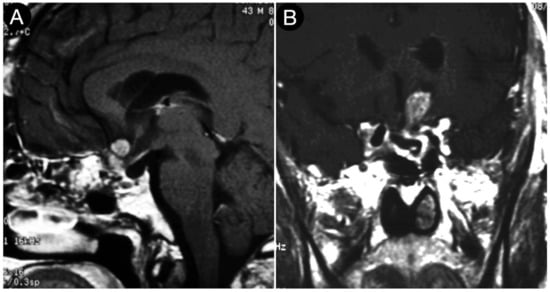

Case #8: Aggressive ACTH Tumor with Multiple Recurrences